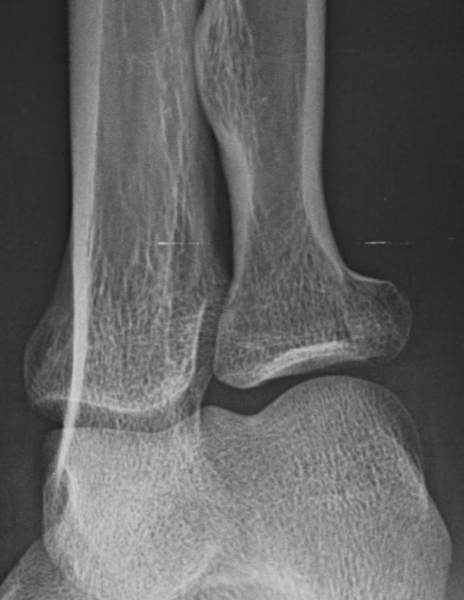

RADIOGRAFIAS AP Y LATERAL DE CODO

LAS PROYECCIONES RADIOLOGICAS OBTENIDAS NOS MUESTRA LOS SIGUIENTES HALLAZGOS:

-Tejidos blandos, a nivel de fosa de codo con aumento la densidad y grosor..

-Almohadilla grasa anterior, con el signo de la vela.

-Radio, con pérdida de la contigüidad a nivel de cabeza que involucra la porción medial, no desplazada. Resto de lo valorado de radio y cubito, sin evidencia de lesiones líticas, blásticas o perdida de la contigüidad.

-De lo valorado de humero, sin evidencia de lesiones líticas, blásticas o perdida de la contigüidad.

-Espacios articulares observados, sin evidencia alteraciones.

OPINIÓN RADIOLÓGICA:

− EN EL PRESENTE ESTUDIO RADIOGRÁFICO, EXISTE FRACTURA A NIVEL DE CABEZA DEL RADIO DE PREDOMINIO MEDIAL CON EDEMA ASOCIADO E INVOLUCRO ARTICULAR (HEMARTROSIS).

− LEER DESCRIPCIÓN Y OTORGAR VALOR DIAGNÓSTICO.

− CORRELACIONAR CON DATOS E HISTORIA CLINICA DEL PACIENTE.